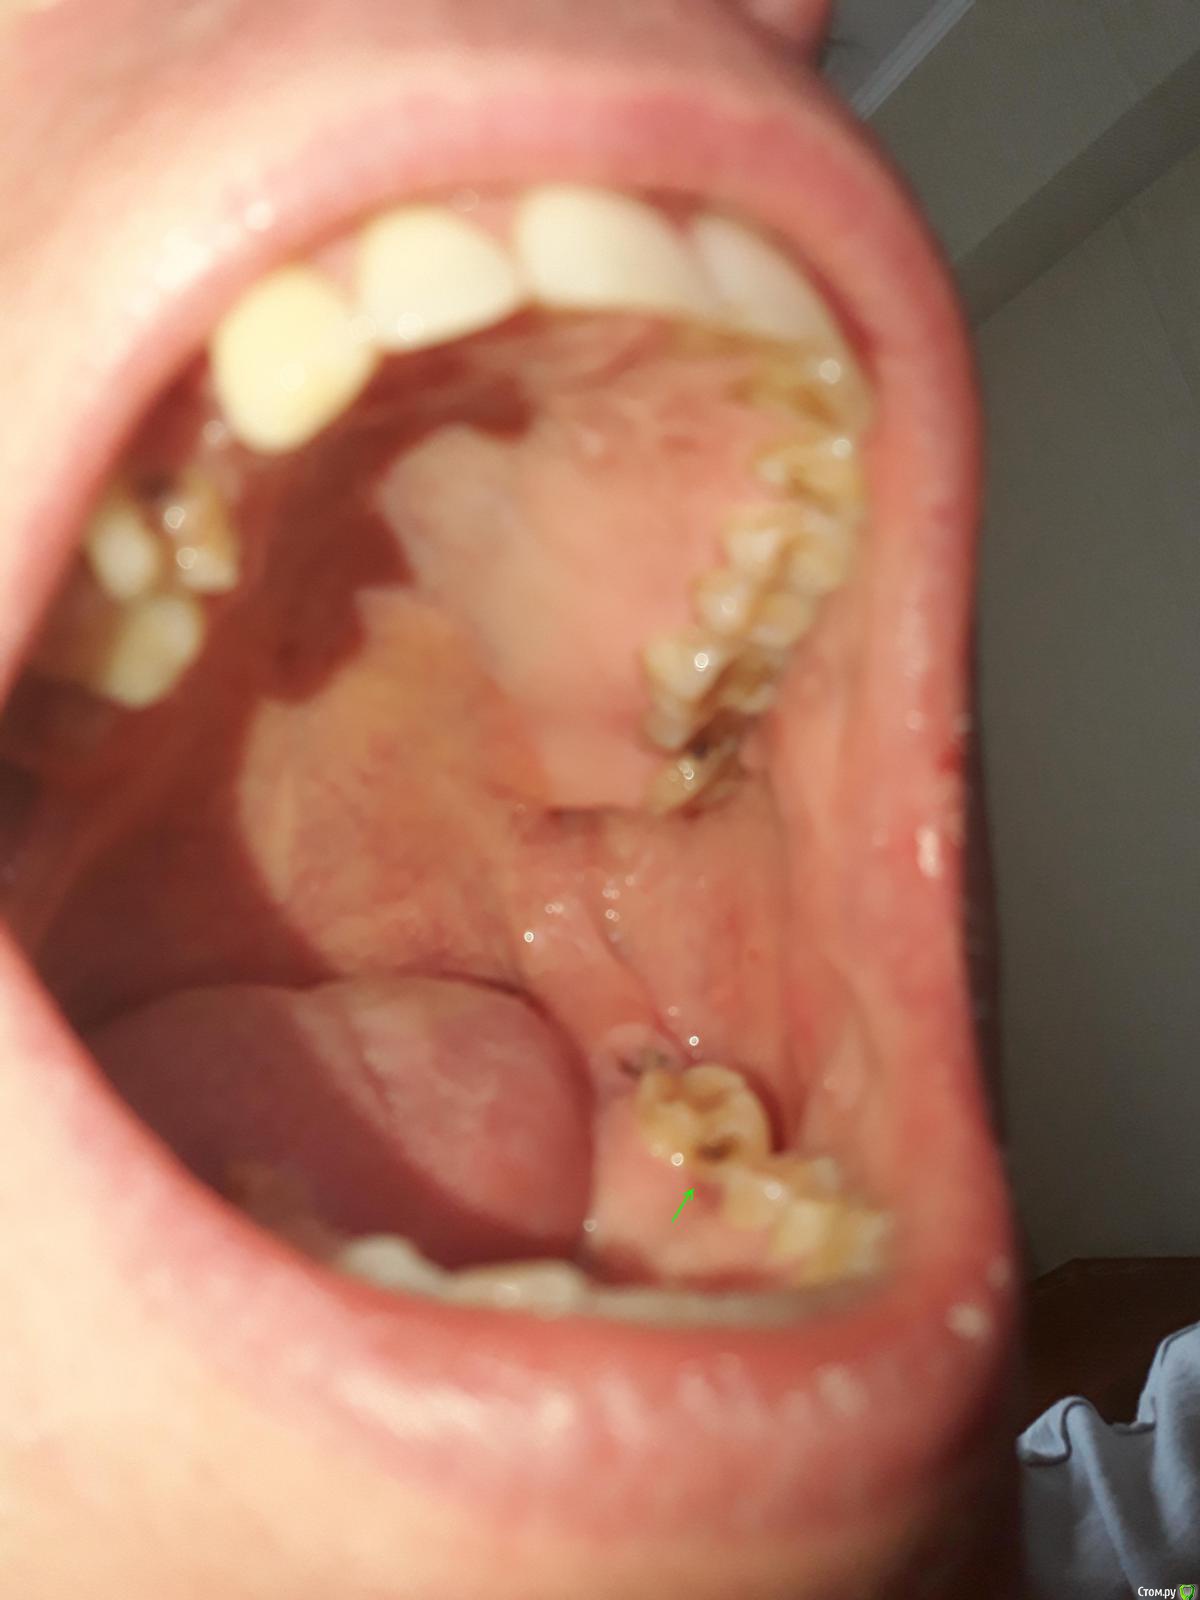

Bond Опубликовано 2 сентября, 2019 Поделиться Опубликовано 2 сентября, 2019 (изменено) Добрый день, уважаемые стоматологи. Имеется такая вот ситуация во рту. Был на приёме, врач проконсультировал и начал лечение, но по некоторым моментам остались вопросы, где-то позиция врача не совсем понятна. Хочу услышать ваши мнения. 1. Что делать с 25-м? Врач уверяет, что протезирование, а тем более удаление, не нужно. Можно восстановить пломбой. Насколько это эстетично? Но главное, какова надёжность? 2. Есть ли шансы у 36-го? Позиция лечащего врача однозначна: удалять. Прошу тут объяснить подробнее. 3. На боковой поверхности 47-го, есть большое ярко выраженное кариозное пятно. Отметил стрелкой. Врач почему-то не считает это проблемой. Дескать, затронута лишь эмаль, дентин не задет, можно пока не трогать. Мне такая позиция кажется странной. 4. Имеет смысл сохранять 38 зуб? Врач считает, что он ещё послужит, хотя я не совсем понимаю как. 5. На 17-м есть небольшой скол кромки зуба, сзади. На снимке не виден. Языком ощущается как углубление с острыми краями. Врач опять же считает, что трогать пока не стоит. Мне кажется, скол лучше заделать пока он небольшой, или я не прав? Изменено 2 сентября, 2019 пользователем Bond Ссылка на комментарий

Bond Опубликовано 4 сентября, 2019 Автор Поделиться Опубликовано 4 сентября, 2019 Большое спасибо! Гляньте пожалуйста ещё фотографии пятна и скола, упомянутых в пунктах 3 и 5. Можно по ним что-то сказать? Ссылка на комментарий